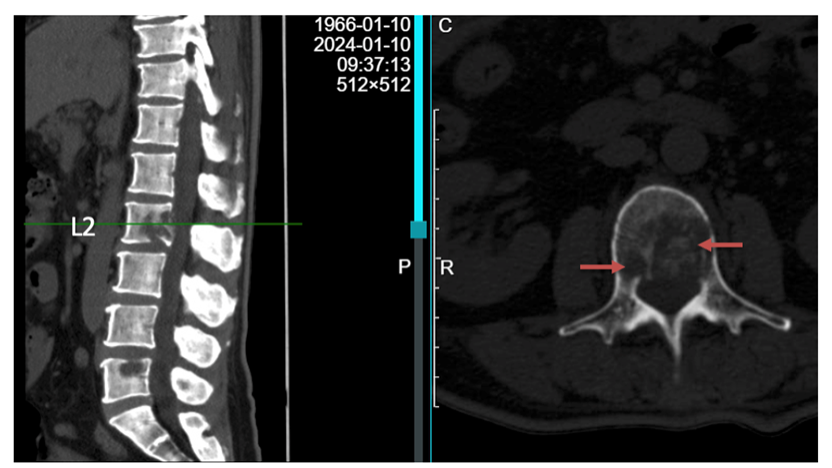

读片:CT及MRI检查提示,T2,L2,L5椎体骨质破坏,红色箭头所指为转移病灶所在位置,可见L2椎体病灶已侵犯后壁,突入椎管内。

患者为胸腰椎多节段的转移,且椎体病灶位置多位于后方,后壁已破损(T2,L2),因此不宜行椎体成形术(存在骨水泥渗漏至椎管风险)。